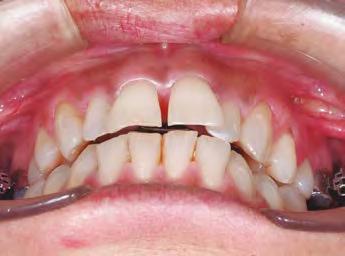

–Corticotomías y Ortodoncia. Ampliando límites del movimiento dental, por la Dra. Aranzazu Senosiain y cols. [50]